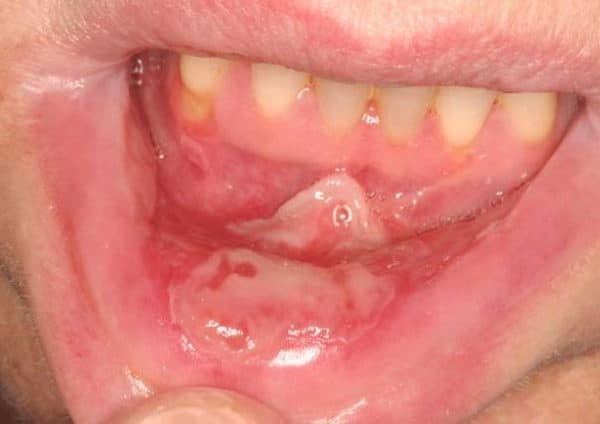

Viêm niêm mạc miệng có rất nhiều triệu chứng khác nhau, có thể kể đến như:

– Khô miệng.

– Nước bọt đặc hơn.

– Lượng dịch nhờn tăng.

– Nướu có tình trạng bóng, sưng hoặc đỏ.

– Xuất hiện các mảng trắng mềm hay mủ trên lưỡi.

– Có vết loét và chảy máu miệng.

– Khi ăn uống có cảm giác nóng nhẹ.

– Khi nói hay nuốt có cảm giác đau.